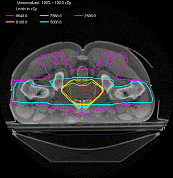

当今进入临床推广应用的最先进的医用电子直线加速器放疗设备。研制IGRT 设备的主要原因是:其一,在单次治疗中,由于病人的自主体内运动,如呼吸可造成心脏器官几个厘米的位置移动,使得病人体内的靶区产生空间位置移动,IGRT 可以动态跟踪这一位置偏移;其二, IGRT 能更有效地进行治疗中或治疗后的质保(QA)和质控(QC),如客观记录放射治疗过程中的含有病人生理组织结构信息的射野图象;其三,在一个疗程或一段时间内,肿瘤的大小和位置会发生改变,IGRT 可以适时调整以适应这些变化。下图显示为通